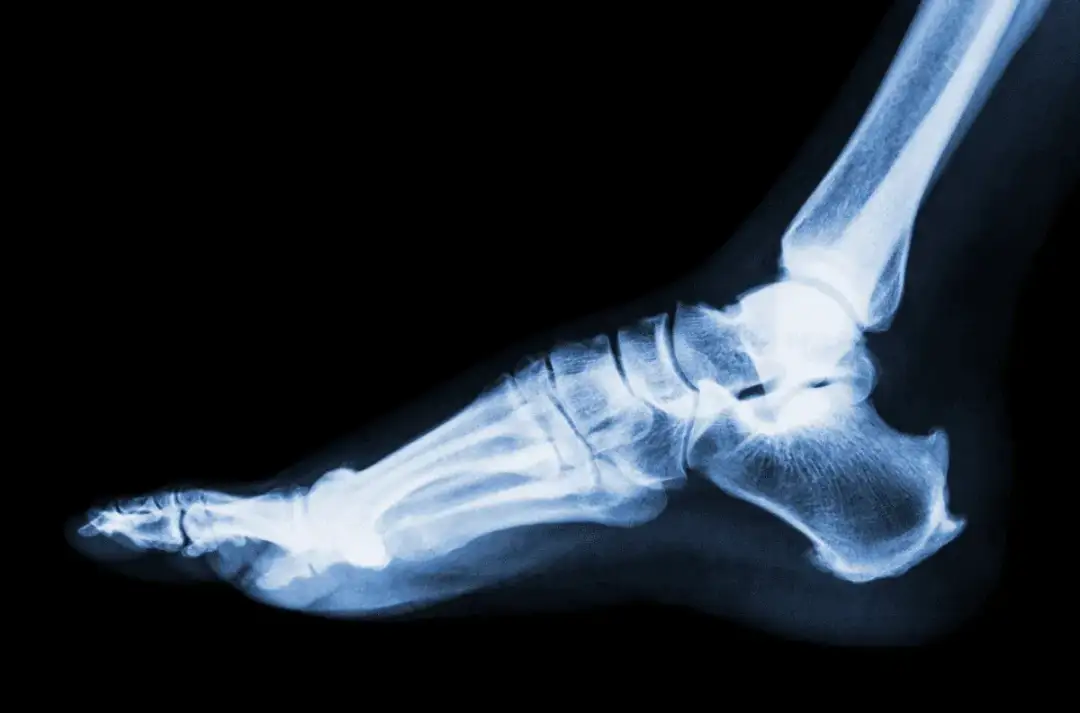

Dowiedz się, ile leczy się skręcenie kostki oraz jakie metody przyspieszają powrót do zdrowia. Sprawdź skuteczne sposoby rehabilitacji i zapobiegania urazom.